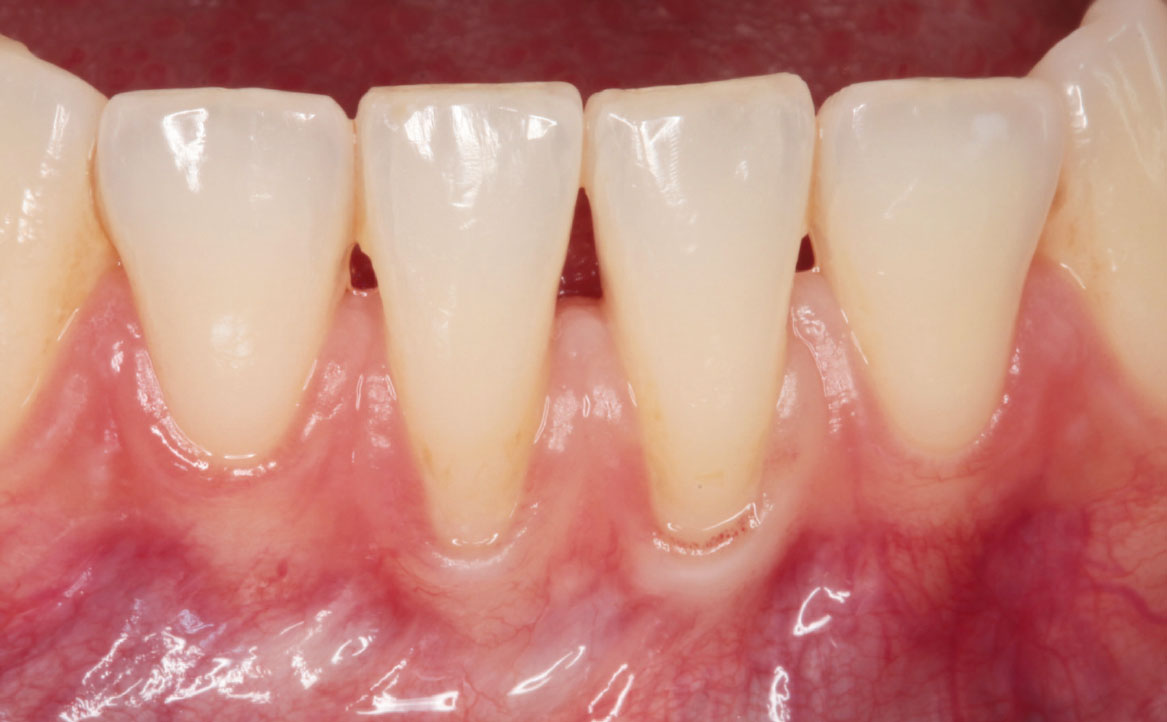

Il caso descritto riguarda una giovane paziente di 31 anni che si è presentata presso l’Unità Operativa di Odontostomatologia dell’Ospedale di Parma per recessioni gengivali di grado I di Miller della superficie vestibolare degli elementi 3.1 e 4.1. La paziente ha riferito deficit di coagulazione congenito e allergia alla mepivacaina.

All’esame obiettivo si è riscontrata scarsità della profondità del vastibolo in zona mandibolare anteriore. Si è deciso perciò di intervenire chirurgicamente eseguendo una vestibuloplastica inferiore con laser Nd:YAG.